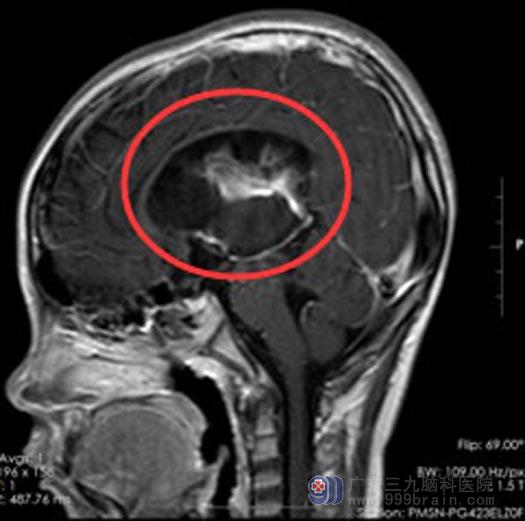

头颅MR检查示“双侧侧脑室占位性病变(以右侧侧脑室为甚),待排畸胎瘤,双侧侧脑室颞角及后角异常信号影沉积,考虑肿瘤破裂可能。

畸胎瘤是一种人体幼稚生殖细胞在胚胎发育时异常分化而产生的肿瘤,由于形似发育异常的“胎儿”而得名“畸胎瘤”。这类肿瘤常长在大脑中线部位,比如三脑室后部、松果体区,容易产生阻塞性脑积水,危及生命。